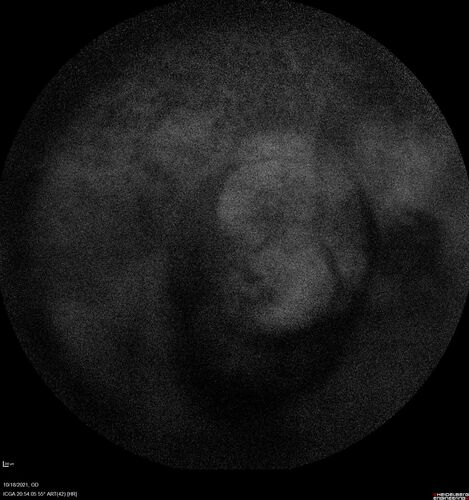

Severe Syphilitic Placoid Chorioretinitis

68 year old man 3 months ago the vision started fading in both eyes.  Just sitting here he can see some light out of his right eye. The patient denies any recent illness or travel.

VA: OD: LP, OS: 4/200

IOP: 9, 13

Anterior segment: 1+ cell/ 2+ flare OU and 2+ NS and anterior vitreous cells

Labs Reactive RPR 1:256, FTA-ABS - reactive - Patient was admitted to hospital for IV PCN and recovered vision almost completely in the left eye and some in the right eye.

See line scans for recovery